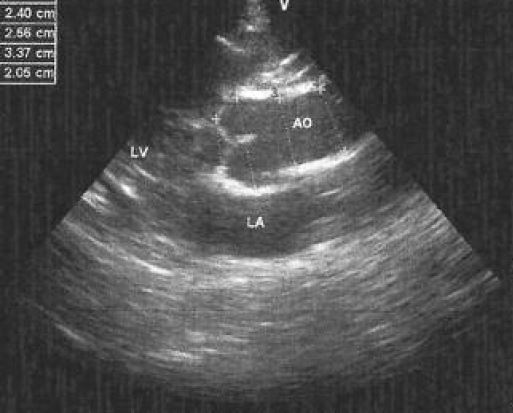

Aşağıdaki resimleri inceleyiniz. İlk resimde hastalığı olmayan bir kişinin ekosu yapılmıştır. AO ile yazan yer hastanın AORT DAMARI dır. 2. resimde ise Marfan hastalığı olan bir kişinin kalp ekokardiyografisi. Dikkat edilirse AO yazan aort damarı genişlemiş ve kapak düzenliliği bozulmuştur. İşte bu yüzden Marfan hastalığında 6 ayda bir eko tetkiki ile takibi gereklidir.